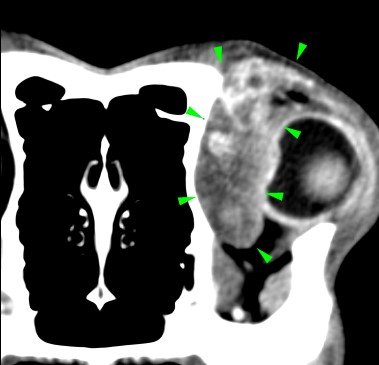

A 7-years-old Labrador was presented to with lethargy, anorexia and exophthalmos.

A CT scan of the head revealed the presence of a soft tissue space-occupying lesion of approximately 3 cm in diameter, arising from the orbital part of the left frontal bone (green arrowheads). The mass was laterally compressing the ipsilateral eye. A focal osteolytic process was observed at the level of the left zygomatic process of the frontal bone (light blue arrowhead).